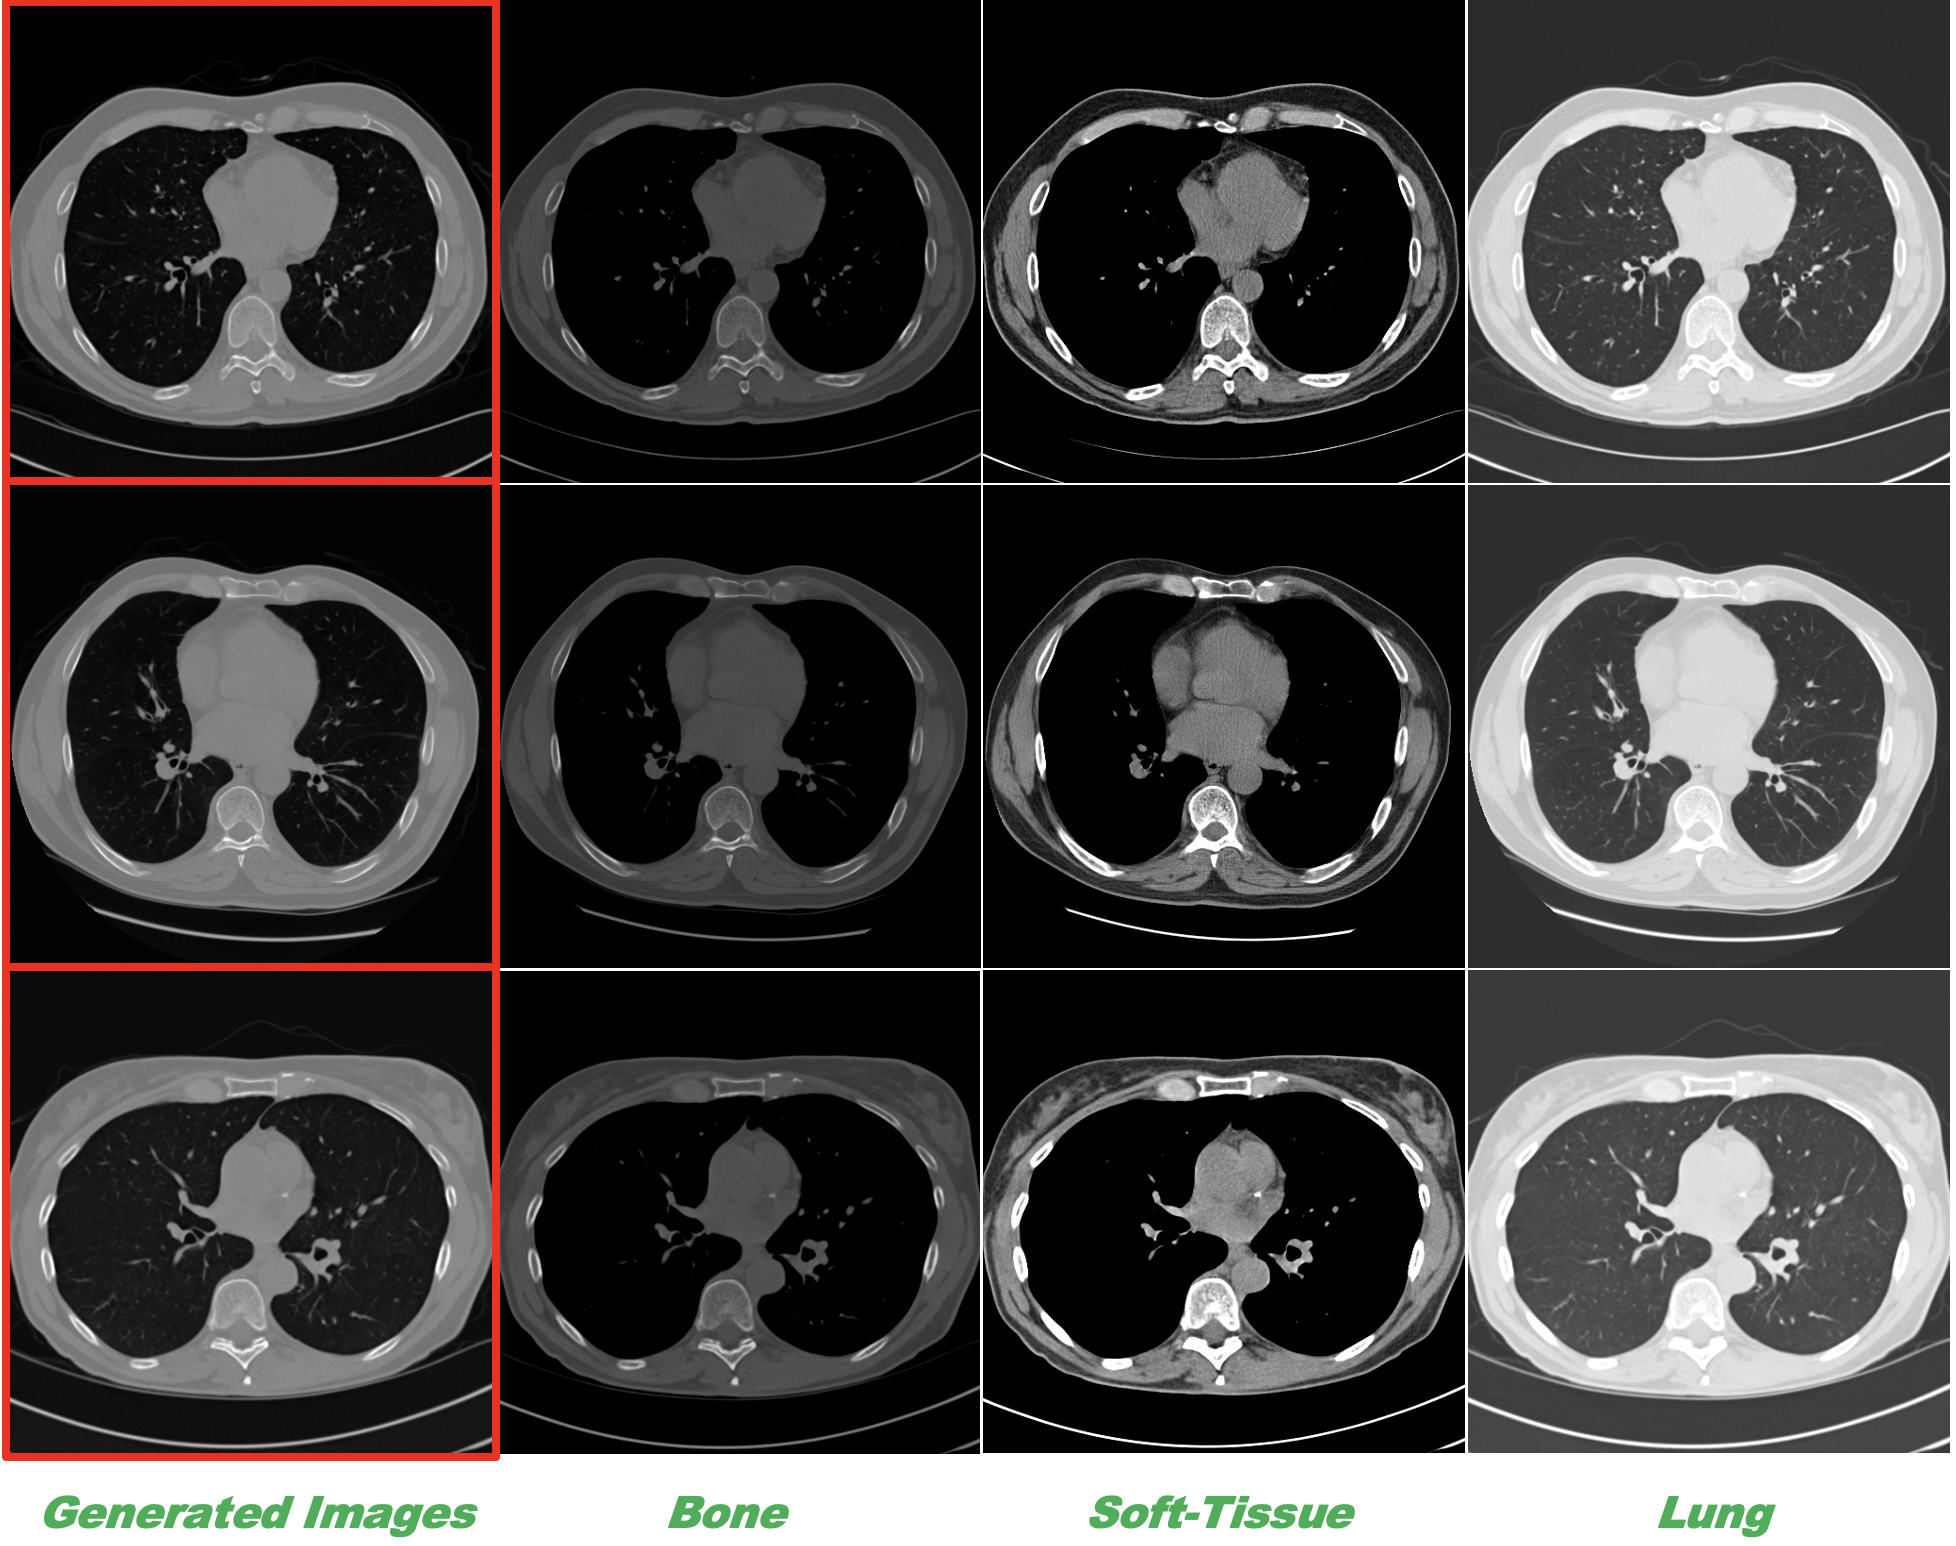

Figs. 2 and 3 showcase images generated with our model. Fig. 2 illustrates sets of guidance images, each comprising an anatomy map and a CT image. These sets serve as conditional (guidance) images for each of the 6 generated images, shown across the center bottom of the figure (see the caption for more detail). The results reveal that diverse anatomically accurate versions of a single CT image can be generated when annotations for the anatomy are available. Here, we generate anatomy maps using B-splines, as detailed in our prior work [4]. It is noteworthy that this approach can be easily extended to simulate pathology/pathology types given a few annotated examples of CT images depicting such pathology. Fig. 3 presents the original full HU window generated images outlined with a red box, along with their decomposition in other clinically relevant windows. Visual inspections affirm their anatomical accuracy in each window, underscoring the effectiveness of DDPMs when assisted by guidance images in learning the nuances of anatomical structures across the entire HU range of lung CT images.